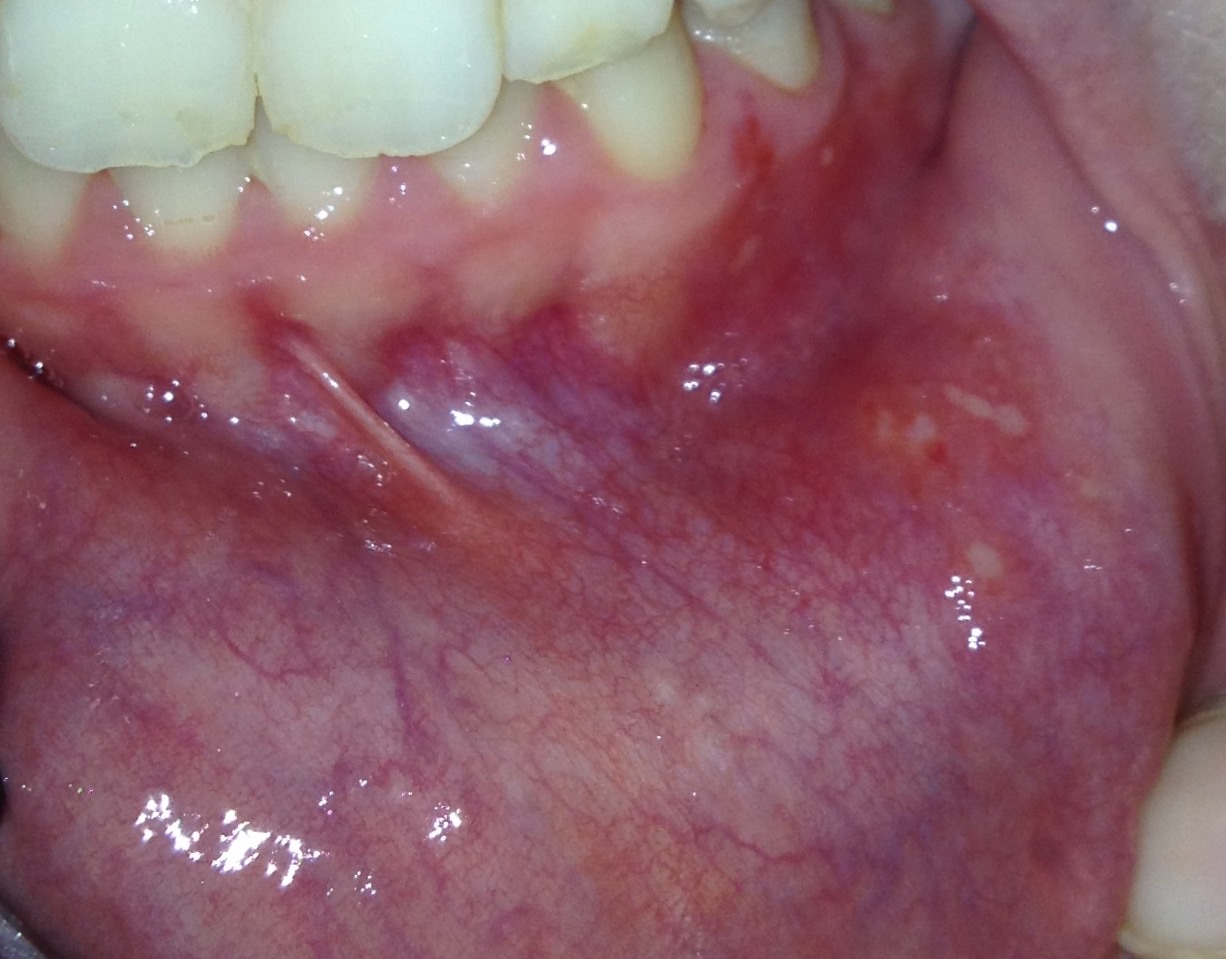

dr gumpert de Zahnmedizin Online Entz ndung im MundTranslate this pageEntz ndung an der Wange Entz ndungen an der Wange k nnen entweder innen von der Mundh hle ausgehen oder sie entstehen von au en Wenn man sich auf die Wange bei t oder wenn scharfe Kanten einer defekten Krone oder Prothese die Wangenschleimhaut reizen dann bildet sich eine schmerzhafte Entz ndung an dieser Stelle Aphten Lippe Innen hilfe de medikamente pyralvex losungTranslate this pageSchmerzhafte und entz ndliche Zust nde des Zahnfleisches und der Mundschleimhaut 3mal t glich die erkrankten Stellen einpinseln Kurzbeschreibung wunde Translate this pageIch versuche es mal so gut wie m glich zu beschreiben Es ist au enrum rot und in der Mitte ein wei er kreis Oft hatte ich es innen an meiner Backe oder lippe jetzt ist es unter meiner Zunge

hilfe de medikamente kamistad gelTranslate this pageTraditionell angewendet als mild wirkendes Arzneimittel bei leichten Entz ndungen des Zahnfleisches und der Mundschleimhaut Bei fehlender Besserung der Entz ndungszeichen innerhalb 1 Woche sowie beim Auftreten unklarer Beschwerden sollte ein Arzt aufgesucht werden Enth lt u a Benzalkoniumchlorid Aphten Lippe Innen wunde Translate this pageIch versuche es mal so gut wie m glich zu beschreiben Es ist au enrum rot und in der Mitte ein wei er kreis Oft hatte ich es innen an meiner Backe oder lippe jetzt ist es unter meiner Zunge this pageHallo whiteshark wenn man einmal auf dei Liste der Inhaltsstoffe sieht wird man evtl verstehen warum man solche Salben Creme nicht unbedingt f r